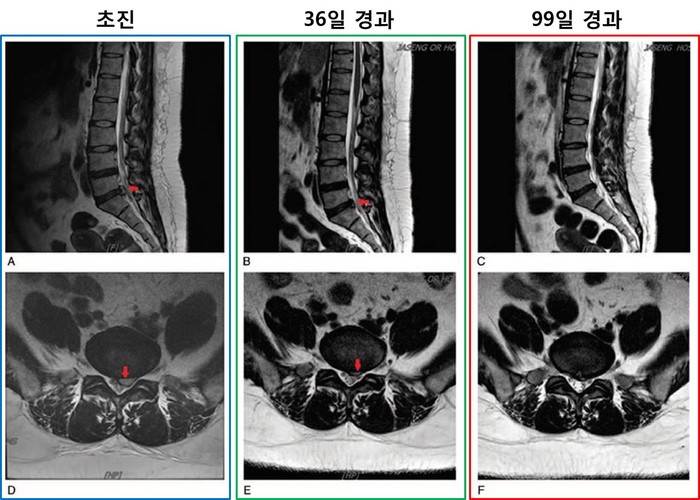

| ▲초진 당시 뚜렷하게 보인 디스크 낭종이 치료 1개월부터 유의미하게 작아졌고 3개월에 이르러서는 완전 흡수됐다. |

그 결과 한·양방 비수술 통합치료를 실시한 지 36일이 지난 1차 평가시점에서 영상의학적으로 유의미한 디스크 낭종의 흡수를 확인할 수 있었고, 99일인 2차 평가에서는 디스크 낭종이 완전히 흡수된 것을 볼 수 있었다. 환자의 요통과 하지방사통의 정도는 초진 당시 NRS 8점 수준이었지만, 치료 한 달 후에는 NRS 1점 수준으로 떨어졌고, 3개월 이후에는 NRS 0점 수준까지 감소해 통증이 완전히 없는 상태에 이르렀다.